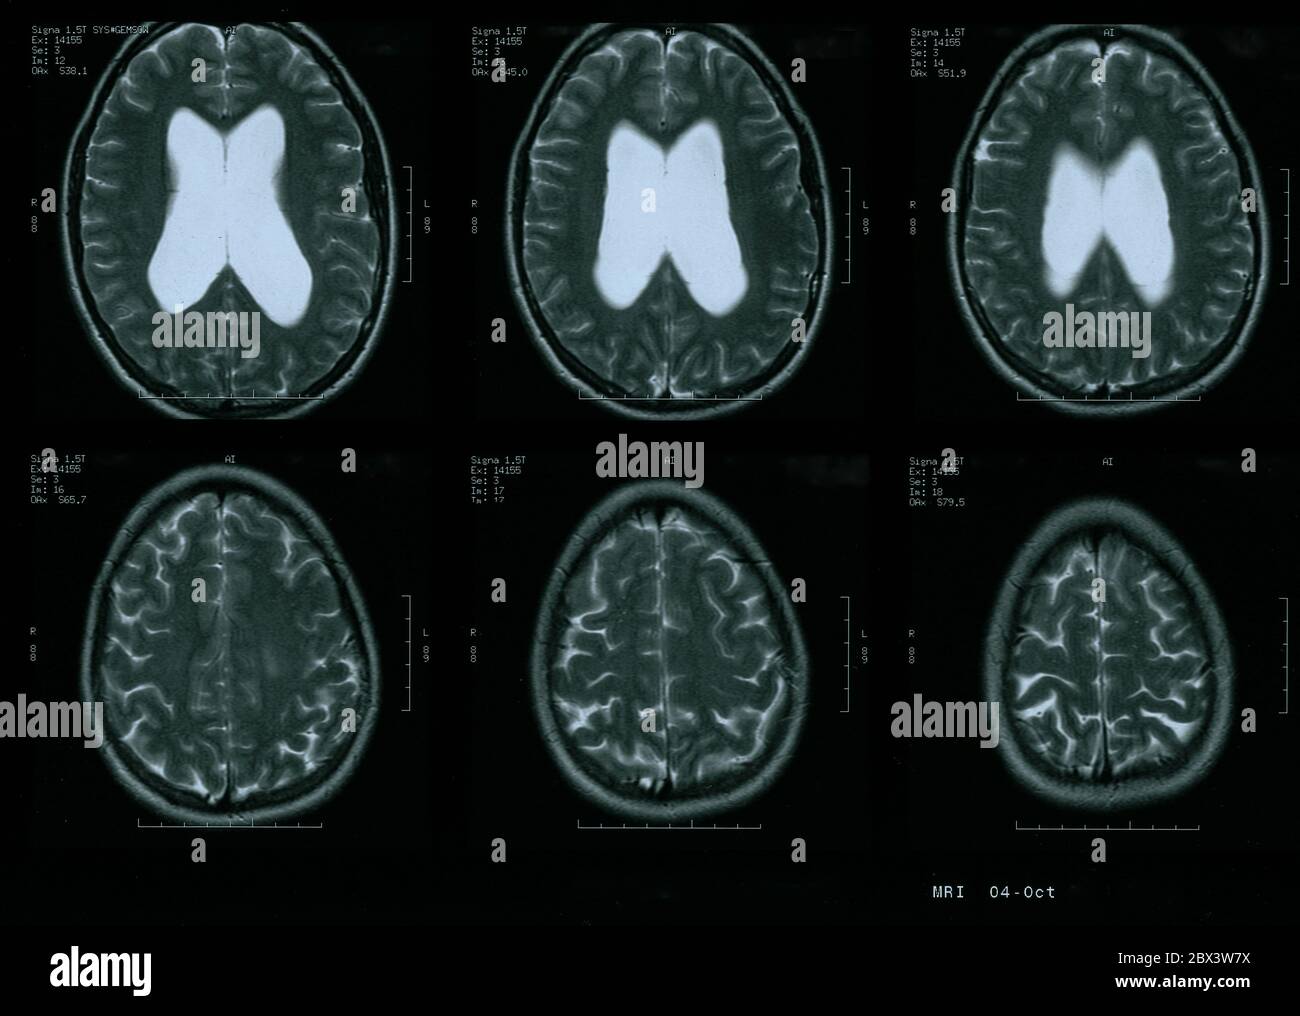

IRM du cerveau de la femme de 35 ans avec un hydrocéphalie léger Banque D'Imageshttps://www.alamyimages.fr/image-license-details/?v=1https://www.alamyimages.fr/irm-du-cerveau-de-la-femme-de-35-ans-avec-un-hydrocephalie-leger-image360274094.html

IRM du cerveau de la femme de 35 ans avec un hydrocéphalie léger Banque D'Imageshttps://www.alamyimages.fr/image-license-details/?v=1https://www.alamyimages.fr/irm-du-cerveau-de-la-femme-de-35-ans-avec-un-hydrocephalie-leger-image360274094.htmlRM2BX3W7X–IRM du cerveau de la femme de 35 ans avec un hydrocéphalie léger

IRM du cerveau de la femme de 35 ans avec un hydrocéphalie léger Banque D'Imageshttps://www.alamyimages.fr/image-license-details/?v=1https://www.alamyimages.fr/irm-du-cerveau-de-la-femme-de-35-ans-avec-un-hydrocephalie-leger-image360274091.html

IRM du cerveau de la femme de 35 ans avec un hydrocéphalie léger Banque D'Imageshttps://www.alamyimages.fr/image-license-details/?v=1https://www.alamyimages.fr/irm-du-cerveau-de-la-femme-de-35-ans-avec-un-hydrocephalie-leger-image360274091.htmlRM2BX3W7R–IRM du cerveau de la femme de 35 ans avec un hydrocéphalie léger